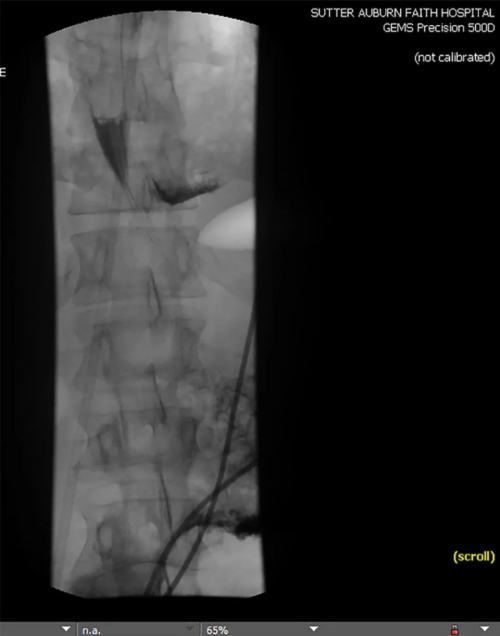

发病后大约12小时 , 上消化道造影发现患者的远端食管左侧穿孔 , 伴造影剂渗漏至纵隔 , 如下图所示 。

文章插图

图2 上消化道造影可见食管管腔外和左侧膈肌周围造影剂渗漏